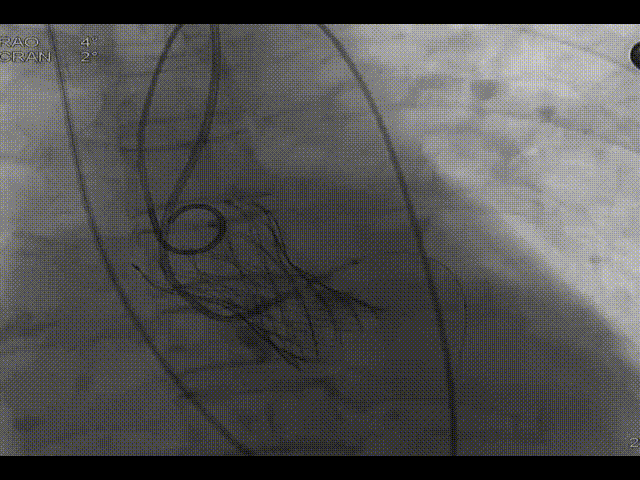

主动脉根部造影

左冠造影及保护

20mm球囊预扩,无漏,冠脉灌注良好